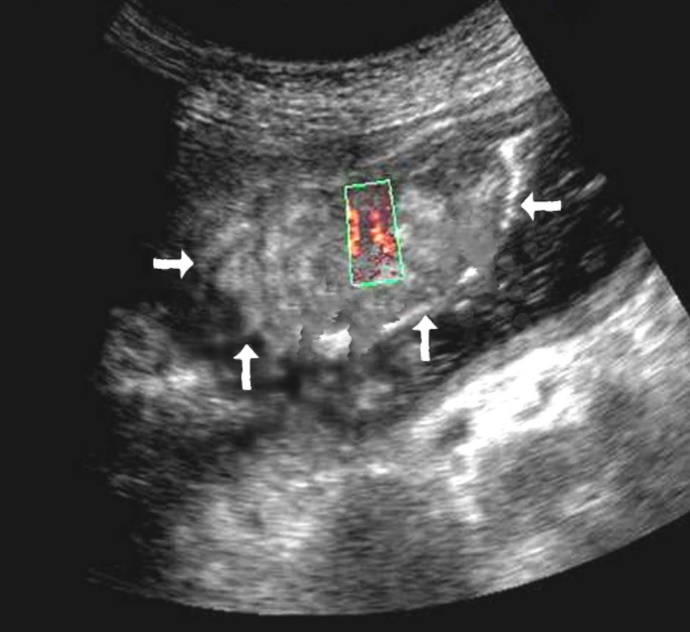

Color Doppler mode was used to assess the nature of the gastric wall lesion in pathologically thickened areas. This method allows the recording of blood flow in the altered areas and using the degree of vascularization to differentiate gastric cancer and other benign changes. Usually in a normal gastric wall it is not possible to visualize the vessels.

Among the 61 patients, pathological vascularization was detected in 42 (68.8%) cases. Of these, all 4 (6.5%) patients with gastric cancer were stage T4 and 38 (62.3%) were stage T3. In 13 cases, vascularization was weak, in 24 cases - moderate, and in 5 cases - enhanced.

Among the 61 patients, pathological vascularization was detected in 42 (68.8%) cases. Of these, all 4 (6.5%) patients with gastric cancer were stage T4 and 38 (62.3%) were stage T3. In 13 cases, vascularization was weak, in 24 cases - moderate, and in 5 cases - enhanced.

Weak vascularization was manifested in the form of a single point color vascular signals, the moderate vascularization - in the form of linear color vascular signals and the enhanced vascularization - in the form of wide color areas inside the tumor (Figure 16, Figure 17).

Figure 16.Distal gastric carcinomas of diffuse infiltrative form of T4 stage. Despite the large size of the tumor the vascularization is manifested in the form of single point color vascular signals.

Figure 17.Gastric carcinomas of infiltrative ulcerative form of Ts stage. Despite the small size of the tumor the vascularization is manifested in the form of wide color areas inside the tumor.